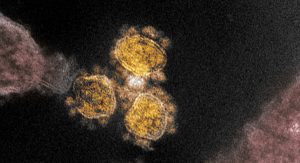

A OMS (Organização Mundial da Saúde) classificou como ‘preocupante’ a variante B.1.1.529 do coronavírus causador da Covid-19 e vai chamá-la de Omicron, informou o órgão após uma reunião do Grupo Consultivo Técnico sobre o Vírus SARS-CoV-2 nesta sexta-feira (26).

Autoridades sanitárias da África do Sul notificaram na quarta-feira (24) a OMS sobre a nova cepa, que é potencialmente mais contagiosa e com múltiplas mutações.

“A situação epidemiológica na África do Sul foi caracterizada por três picos distintos nos casos notificados, o último dos quais foi predominantemente a variante Delta. Nas últimas semanas, as infecções aumentaram abruptamente, coincidindo com a detecção da variante B.1.1.529. A primeira infecção B.1.1.529 confirmada conhecida foi de uma amostra coletada em 9 de novembro de 2021”, diz a OMS em comunicado.

A Omicron passa a integrar a lista de variantes de preocupação, que é composta pelas variantes Alfa (Reino Unido), Beta (África do Sul), Gama (Brasil), e Delta (Índia).

A nova variante foi detectada nos últimos dois dias, com o aumento de infecções nas cidades de Pretória e Joanesburgo, capital e centro econômico da África do Sul, respectivamente. Já foram registrados casos também em Hong Kong, Israel e Botsuana.